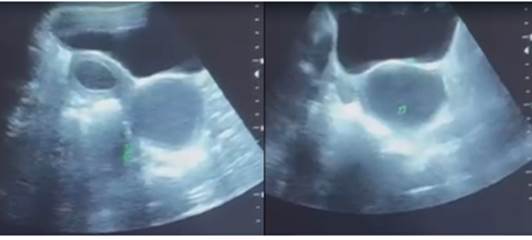

Se trata de escolar femenina de 9 años de edad, con diagnóstico de malformación ano rectal (ano anterior), que ameritó anorectoplastia sagital posterior a los 2 años, y agenesia renal derecha documentada a los 7 años. Acudió por dolor pélvico intenso un mes posmenarquia, asociado a sangrado genital escaso, al examen físico, el abdomen estaba doloroso a predominio en hipogastrio, la membrana himeneal era anular y la vagina estaba permeable. El ultrasonido pélvico transabdominal 2D y 3D, mostró evidencia de útero doble, el útero derecho y la hemivagina derecha (no comunicante) con hematómetra y hematocolpos; el útero izquierdo de aspecto normal (Figuras 1, 2 y 3).